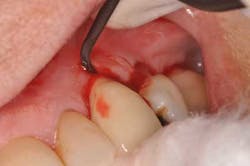

A new patient presents to my office with a chief complaint: “My implant crown fell off yesterday.” She’s a 72-year-old woman with noncontributory medical history. She states the implant in tooth position No. 11 was placed “a few years ago and never felt right.” Examination reveals a prefabricated abutment of some sort that is not mobile. Curiously, the peri-implant gingiva has a slight erythema. Moderate bleeding is noted upon insertion of the implant crown.

Fig. 1: Implant crown seated.

Fig. 2: Moderate bleeding noted around prefabricated abutment after crown is removed.